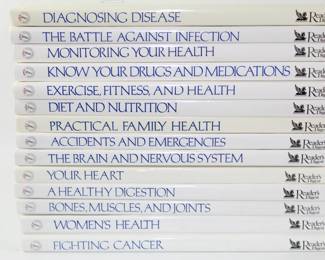

1126 - Home Medical Library